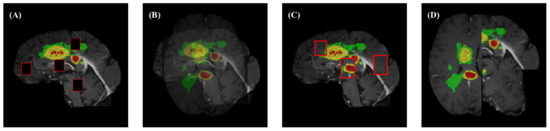

4.2. Segmentation Results